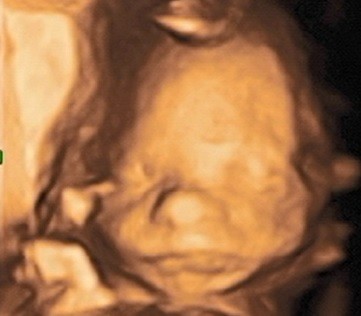

SuperJestem po dzisiejszych badaniach prenatalnych, stres już opadł bo wszystko jest w porządkumały waży 440g więc ok, rośnie zdrowy chłopak

próbowaliśmy uchwycić zdjęcie w 4D ale nie było łatwo, zasłaniał się rączkami i nóżkami, ale coś wyszło, pochwalę się

Zobacz załącznik 955672

Duży chlopiec :*